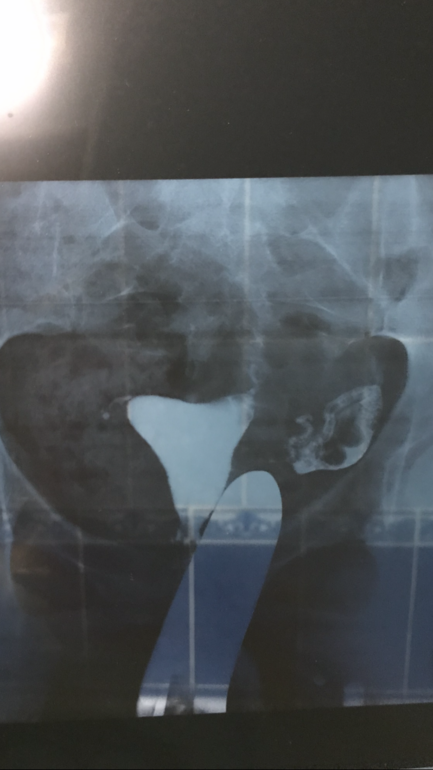

Можно с такими снимками планировать?

В том: что как вы думаете есть ли шансы забеременеть с такой трубой? ( глядя на снимки) или там совсем все плохо?

Ну мне с телефона плохо видно, но жидкость трубу прошла. Как уж она ее проходила, может не сразу... Но в целом, картина спаечного процесса вроде вырисовывается.

А как понять где спаечный процесс? Где он прорисовывается?( в чем это выражено? Объясните мне пожалуйста 🙏🏼Хочу понять

Это вот в конце трубы где? Где якобы жидкость вышла? Там да

Там где жидкость скопилась, там спайки. В идеале, жидкость должна свободно растечься по брюшине.

Спайки же могут быть где угодно и различные, если есть на выходе из трубы, то с большой долей вероятности, есть и в ней самой (возможно жидкостью пробили, такое бывает часто).

Нет, в брюшной полости не мешают, если не распространяются на область труб и яичников. У Вас видимо спаяна труба на выходе была и спаечный процесс в прилегающих тканях. Ну и потому и жидкость не растеклась как положено, а скопилась в одном месте. А мешает ли такое зачатию, кто ж скажет...в целом, труба извилиста, но проходима, пробуйте.

Ну и конечно Ваши страхи понятны. Тем более, судя по снимку, у Вас одной трубы уже нет.

Вот у меня по трубе спокойно прошло врач сказала. А потом в конце встала в трубе

Потом врач под давлением больше жидкости пустила и видимо пробила🤷🏼♀️

Есть шансы, потому что она у вас судя по снимку проходима. А что написано в заключении?